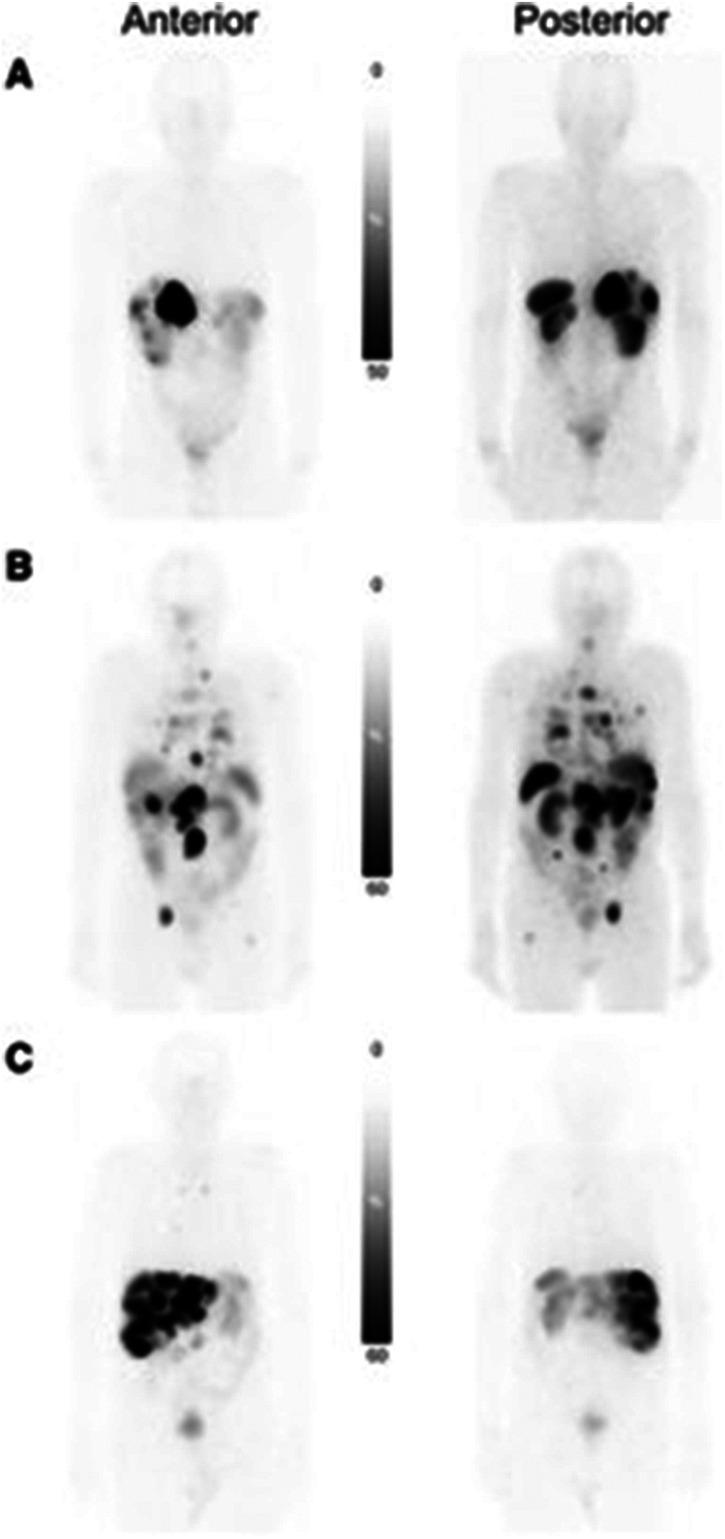

Neuroendocrine tumors (NETs) are a heterogeneous group of neoplasms characterized by their overexpression of somatostatin receptors (SSTRs), which can be utilized for peptide receptor radionuclide therapy. This review provides a comprehensive update on the clinical trials of radiolabeled SSTR-targeting radiopharmaceuticals since 2020, with a focus on somatostatin receptor agonists and antagonists radiolabeled with Ga, F, Tc, Lu, Tb, Pb, Cu, and Ac. Head-to-head clinical trials demonstrate that radiolabeled SSTR antagonists such as [Ga]Ga-DOTA-JR11 and [Ga]Ga-DOTA-LM3 offer improved lesion detection and tumor-to-background ratios (particularly in liver metastases) compared to radiolabeled agonists like [Ga]Ga-DOTA-TOC and [Cu]Cu-DOTA-TATE. Additionally, F-labeled agents offer logistical and dosimetric advantages over Ga, due to F's longer half-life and cyclotron production, allowing for delayed imaging and increased availability to a wider range of patients. Emerging targeted alpha therapy agents, including [Ac]Ac-DOTA-TATE, show promising results in treating disease resistant to conventional therapies due to the high linear energy transfer of alpha particles, which leads to improved localized cytotoxicity. Collectively, these developments support a shift toward more precise, receptor-specific theragnostics, emphasizing the need for further head-to-head clinical trials and integration of dosimetry-driven, personalized treatment planning in the management of NETs.

神经内分泌肿瘤(NETs)是一组异质性肿瘤,其特征在于生长抑素受体(SSTRs)的过度表达,可用于肽受体放射性核素治疗。本综述全面更新了自2020年以来放射性标记的靶向SSTR放射性药物的临床试验情况,重点关注用镓(Ga)、氟(F)、锝(Tc)、镥(Lu)、铽(Tb)、铅(Pb)、铜(Cu)和锕(Ac)标记的生长抑素受体激动剂和拮抗剂。头对头临床试验表明,与[Ga]Ga-DOTA-TOC和[Cu]Cu-DOTA-TATE等放射性标记激动剂相比,[Ga]Ga-DOTA-JR11和[Ga]Ga-DOTA-LM3等放射性标记SSTR拮抗剂在病变检测和肿瘤与背景比值方面表现更佳(尤其是在肝转移瘤中)。此外,由于F的半衰期更长且可通过回旋加速器生产,F标记的药物在后勤和剂量学方面比Ga具有优势,这使得可以进行延迟成像并让更多患者能够使用。新兴的靶向α治疗药物,包括[Ac]Ac-DOTA-TATE,由于α粒子的高线性能量传递导致局部细胞毒性增强,在治疗对传统疗法耐药的疾病方面显示出有前景的结果。总体而言,这些进展支持向更精确、受体特异性的诊疗方法转变,强调在NETs管理中需要进一步进行头对头临床试验以及整合剂量学驱动的个性化治疗方案。